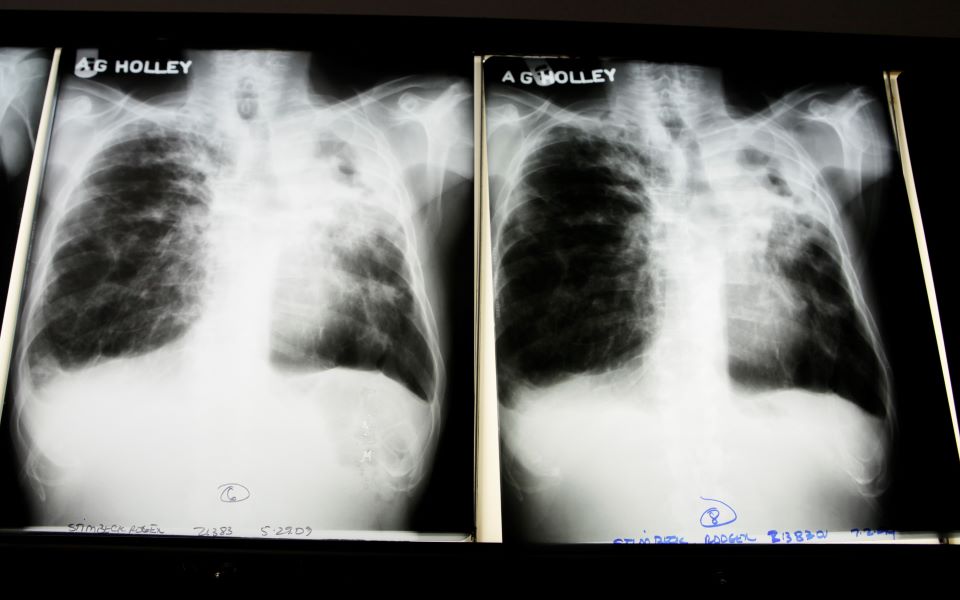

Ανατρέποντας ένα ιατρικό δόγμα αιώνων, Νοτιοαφρικανοί επιστήμονες βρήκαν ότι η αναπνοή συμβάλλει περισσότερο από τον βήχα στην εξάπλωση της φυματίωσης. Μέχρι σήμερα ο βήχας θεωρείτο η βασική οδός μετάδοσης του βακτηρίου (Mycobacterium) που προσβάλλει συνήθως τους πνεύμονες και προκαλεί τη φυματίωση.

Η φυματίωση είναι η πιο θανατηφόρα λοιμώδης νόσος στον κόσμο μετά την Covid-19, προκαλώντας περισσότερους από 1,5 εκατομμύρια θανάτους ετησίως. Πέρυσι μάλιστα καταγράφηκε η πρώτη αύξηση θανάτων εξαιτίας της μετά από μία δεκαετία, σύμφωνα με τον Παγκόσμιο Οργανισμό Υγείας (ΠΟΥ).

Το 2020 περίπου 5,8 εκατομμύρια άνθρωποι στον κόσμο διαγνώστηκαν με φυματίωση, όμως ο ΠΟΥ εκτιμά ότι στην πραγματικότητα οι μολύνσεις ήταν σχεδόν 10 εκατομμύρια. Οι επιστήμονες του Πανεπιστημίου του Κέιπ Τάουν στη Ν. Αφρική εκτιμούν ότι ένα μεγάλο ποσοστό των μολύνσεων συμβαίνει αερογενώς, χωρίς να γίνεται αντιληπτό. Αυτό πιθανότατα εξηγεί γιατί οι κλειστοί χώροι με πολλούς ανθρώπους -όπως οι φυλακές- αποτελούν γόνιμο πεδίο εξάπλωσης της φυματίωσης, όπως άλλωστε και της Covid-19.